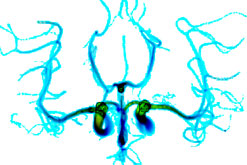

brain blood flow patterns modelled using grid computing

Supercomputers are not the only way of harnessing processing power - another option is to hook up computer systems across a nation, or even between countries. A worldwide grid is about to be launched which will process all the data from the LHC at CERN in Geneva. Steve Lloyd from Grid PP, the UK grid for particle physics, joins Simon to explain the power of the grid. And reporter Nick Balneaves visits the National Hospital for Neurology and Neurosurgery in London, where grid computing is being used to model blood flow patterns in the brain - a development brain surgeon Stefan Brew believes could revolutionise the way he works.